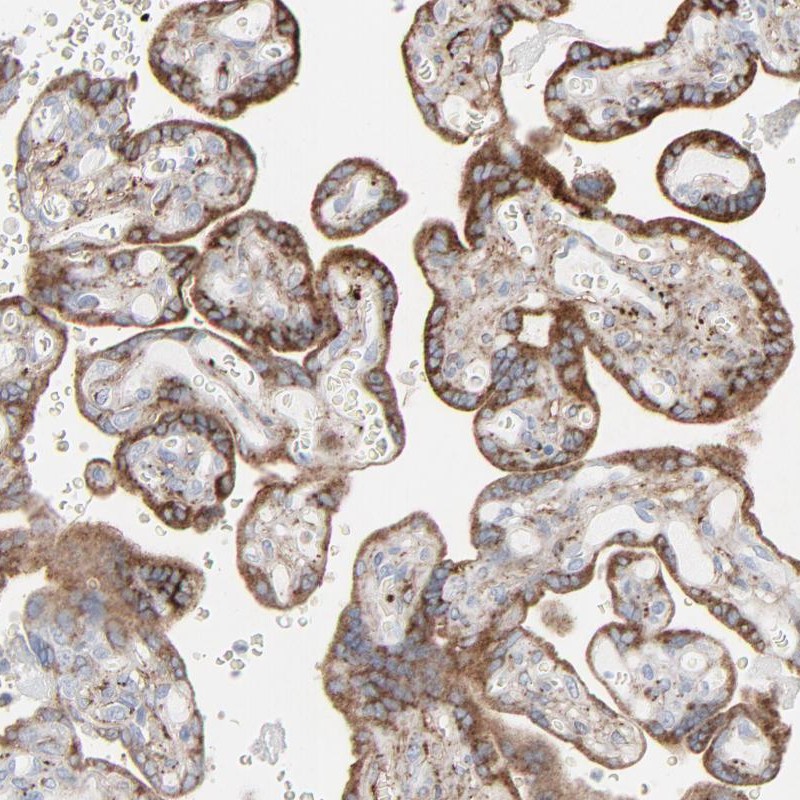

Immunohistochemistry is used for validating antibody reliability by assessing staining pattern in 44 normal tissues. Validation scores include Enhanced, Supported, Approved and Uncertain.

Results of validation by standard or enhanced validation based on assessment of antibody performance in 44 normal tissues.

Standard validation results in scores Supported, Approved or Uncertain. An image representative of the antibody staining pattern is shown.

Conformance of the expression pattern with available gene/protein characterization data in scientific literature and data from bioinformatic predictions.

Partly consistent with extensive gene/protein characterization data.

Consistent with extensive gene/protein characterization data.

Medium consistency between antibody staining and RNA expression data.